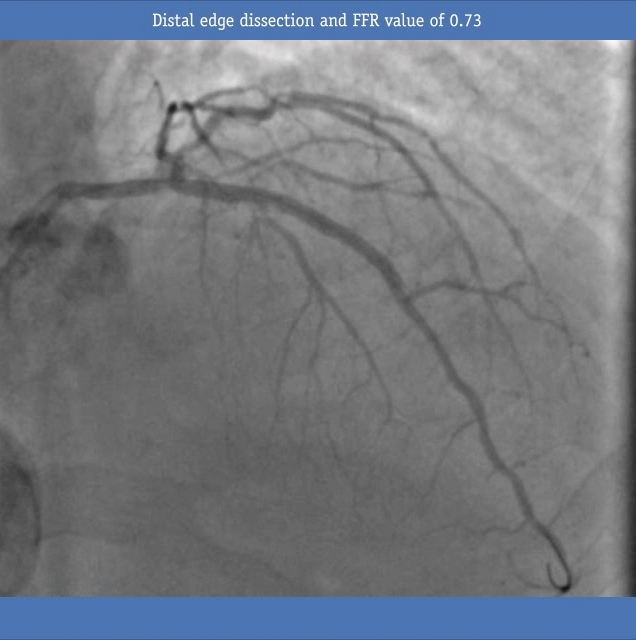

Post Stenting FFR performed, edge dissection discovered

• COMET™ was reconnected and IC adenosine was administered, giving an FFR value of 0.73. After further analysis an edge dissection was discovered at the distal stent edge.